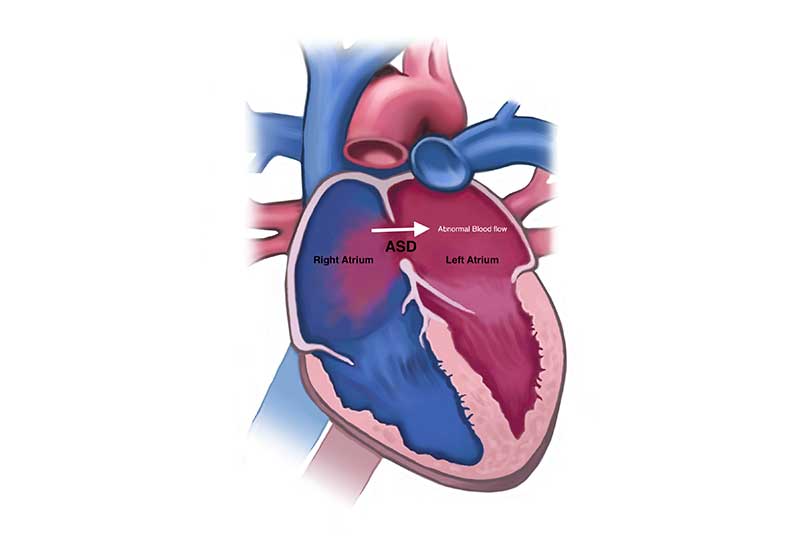

قیمت: 52٬500 تومان - دسته بندی فایل: پاورپوینتدانلود پاورپوینت نقص سپتوم دهلیزی

خرید پاورپوینت حرفه ای با موضوع نقص سپتوم دهلیزی از لوکس فایل